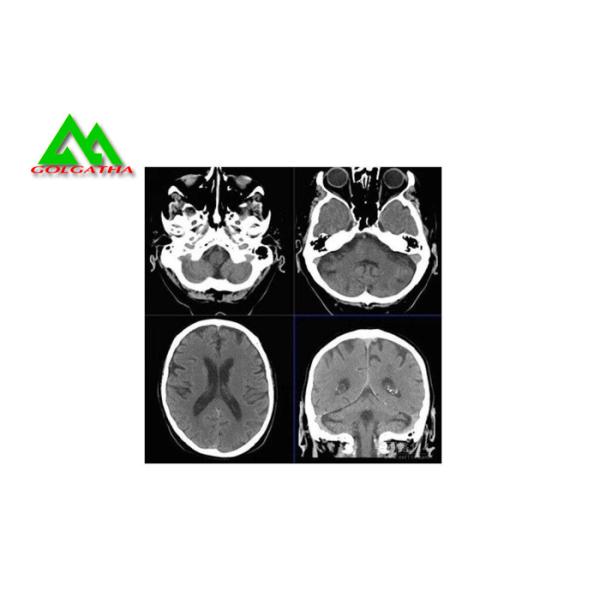

Medical X-ray Film

Product Description

Features:

1) Application: High-speed rare-earth sensitization-developing screens and calcium tungsten acid sensitization-developing screens

2) High sensitivity under low exposure, specific curve copes with all sensitization conditions

3) Low density soft tissue can be clearly seen, such as lungs, retro cardiac mediastinum, transverse diaphragm and spinal marrow, the slightest blood vessels can be pictured clearly

High Sensitivity Medical X Ray Film X Ray Room Equipment Accessories All Size Images |